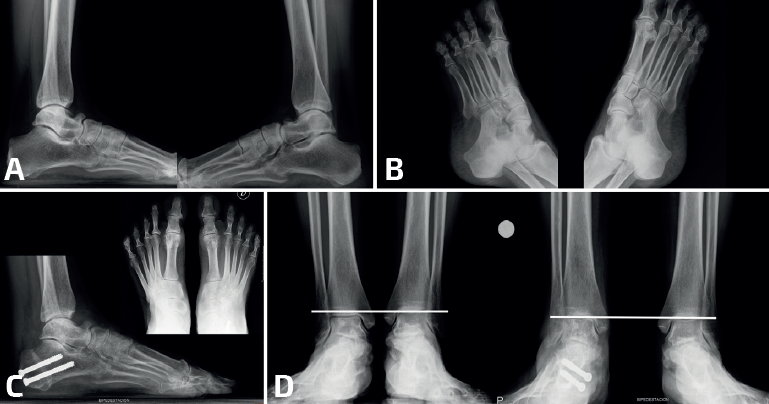

mact.1701.fs2403007-figura6.png

Figura 6. En el caso presentado en la Figura 3 con una coalición calcaneocuboidea bilateral (A: proyección lateral; B: proyección oblicua), realizamos una osteotomía varizante de unos 10 mm de desplazamiento medial (C) y la paciente se recuperó clínicamente para llegar a estar asintomática al año de la intervención. También recuperó radiológicamente la altura talar (D) si comparamos la radiografía preoperatoria con la del año del postoperatorio. La recuperación de la altura del tobillo se produce a través de las articulaciones móviles pericoalición.